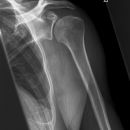

Schulter a.p. (Schultergelenk nach Grashey)

- Außenrotation ->Tuberculum majus lateral randbildend, Innenrotation ->Tuberculum minus medial randbildend

- Gelenkspaltweite 4-6 mm

- Weite des subacromialen Raumes exakt nur in der 10 – 15° nach kaudal angulierten Aufnahme bestimmbar ("Morrison, Outlet View")! Normalerweise 1 - 1,5 cm, < 6 mm -> wohl pathologisch, Impingment röntgenlog. wahrscheinlich, Cave. rein klinische Diagnose!

- Normvarianten: Os glenoidale (akzessorischer Ossikel kaudal des Glenoids), persistierende Akromion- oder Korakoidapophyse, entwicklungsbedingte Pfannenranddefekte